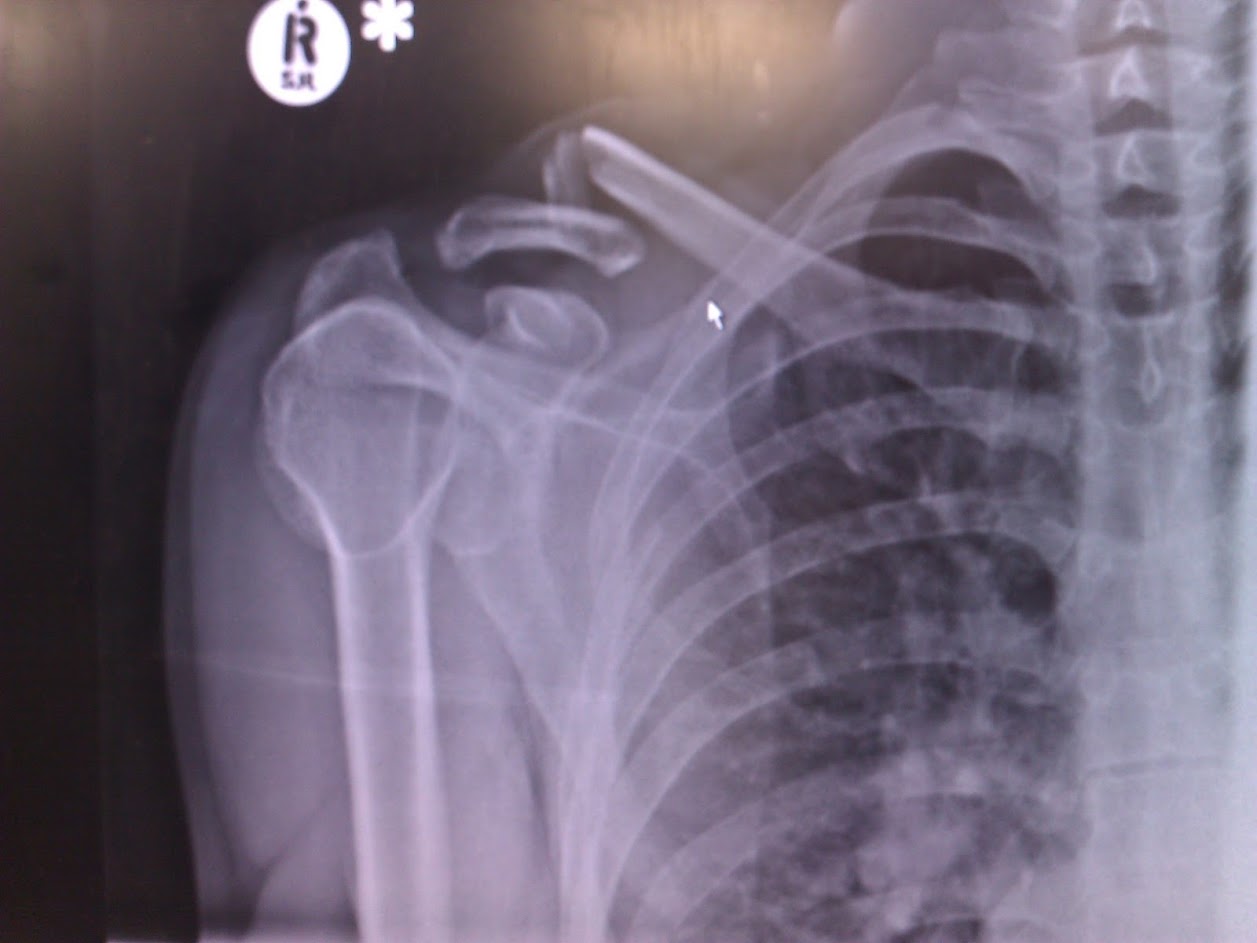

smiley drunk elbow

[URL= http://i239.photobucket.com/albums/ff167/LukeBurstow/c0225524-6513-4745-9946-43acf41c7ddd_zpsmqdlej7s.jp g" target="_blank">

http://i239.photobucket.com/albums/ff167/LukeBurstow/c0225524-6513-4745-9946-43acf41c7ddd_zpsmqdlej7s.jp g"/> [/IMG][/URL]